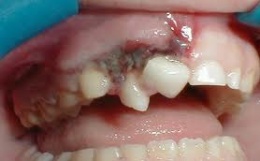

Son variados los tipos de lesiones que pueden producirse en los dientes provocados por traumas: las fracturas o roturas de las coronas ,desplazamientos dentarios (luxaciones) , la salida total del diente de la boca (denominadas avulsiones dentarias), las fracturas de las raíces, y pueden aparecer combinaciones de estas.

Por leve que pueda parecer la lesión, se impone acudir de inmediato al estomatólogo, para recibir la debida valoración y el tratamiento adecuado. Para el pronóstico de los dientes traumatizados, es de vital importancia, que un adecuado tratamiento sea efectuado lo más pronto posible después del trauma. Se recomienda atraer la atención de padres, representantes, educadores y profesionales de la salud, enfatizando que siempre que ocurran estos accidentes desafortunados se debe acudir al estomatólogo, y no solamente cuando existe dolor o se ha perdido la estética.